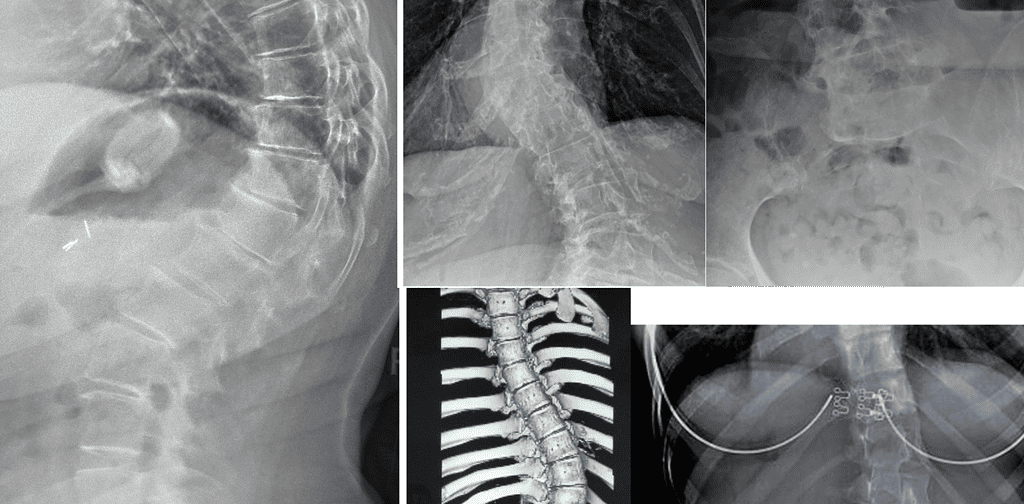

Measurable outcomes on X-ray. Here is what our co-managed patients have experienced.

Note: Individual results vary. All measurements taken on calibrated standing AP radiographs by the treating doctor. Cases shown with patient/guardian consent.